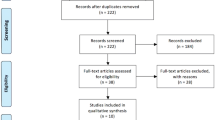

LLS was first introduced in our center in October 2011, and RLS has been performed since February 2020. All patients undergoing liver surgery are included in a prospectively maintained electronic database regarding patient demographics, indication for surgery, intraoperative details and postoperative course. For the current analysis, we included all minimally invasive liver resections from 2011 to October 2022, aiming to compare robotic-assisted resections with conventional laparoscopic procedures. Additionally, the percentage of open resections before and after the introduction of robotics was compared. Patients who underwent ablation procedures, cyst fenestrations or a biopsy without an additional resection, were not included in the current analysis (Fig. 1). This study received approval from our institutional ethics committee (B3962022000047).

During the study period, a total of 629 patients underwent a minimally invasive hepatectomy. This included 452 patients who underwent a conventional laparoscopic procedure and 177 patients who underwent a robotic procedure. In this period, 220 other patients underwent an open partial hepatectomy. Since the introduction of robotic surgery in our center, 11.5% of patients (31 out of 270) undergoing liver surgery had an open resection versus 32.6% (189 out of 579) in the era of conventional laparoscopy (P < 0.001) (Fig. 3).